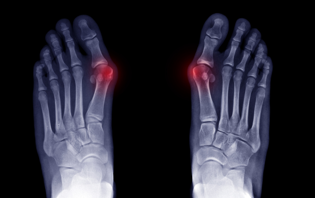

- Orthopedics